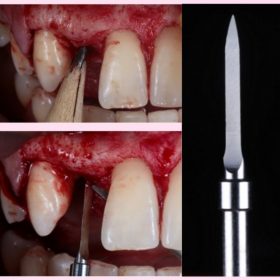

Step 3: Surgical steps from incision to implant placement.